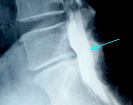

ミエロ

「骨の隙間が狭いので椎間板ヘルニアです。」 ?

椎間板が狭いのは椎間板が変性しているためですが、必

ずしもヘルニアがあるとは限りません。右は腰椎の造影検査

ですが、矢印の部分は椎間板が狭くてもヘルニアにはなって

おりません。この部分のこの変化は多くの人で見られます。